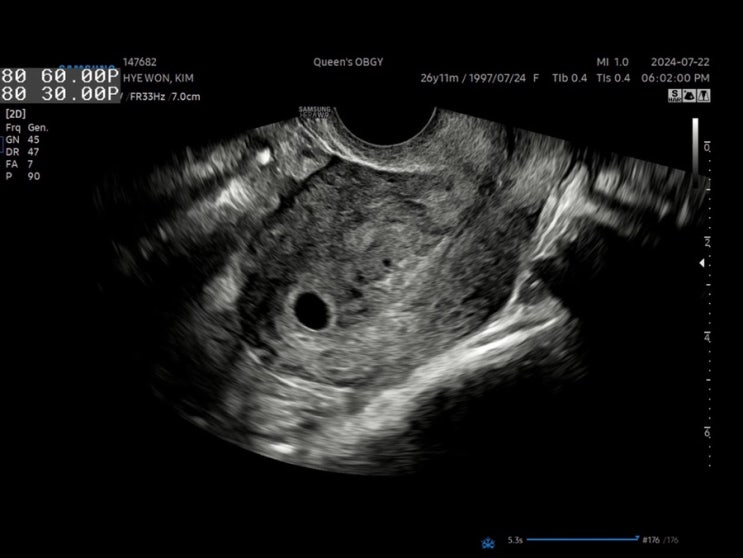

[임신 이야기_2] 1트에 임신, 근데 이제 자궁내막 증식증을 곁들인

나는 임신 준비라고 할 것도 없이 한 번에 미뇽이가 찾아왔다. (나이스) 아닌가? 치료했던 게 임신 준비인...